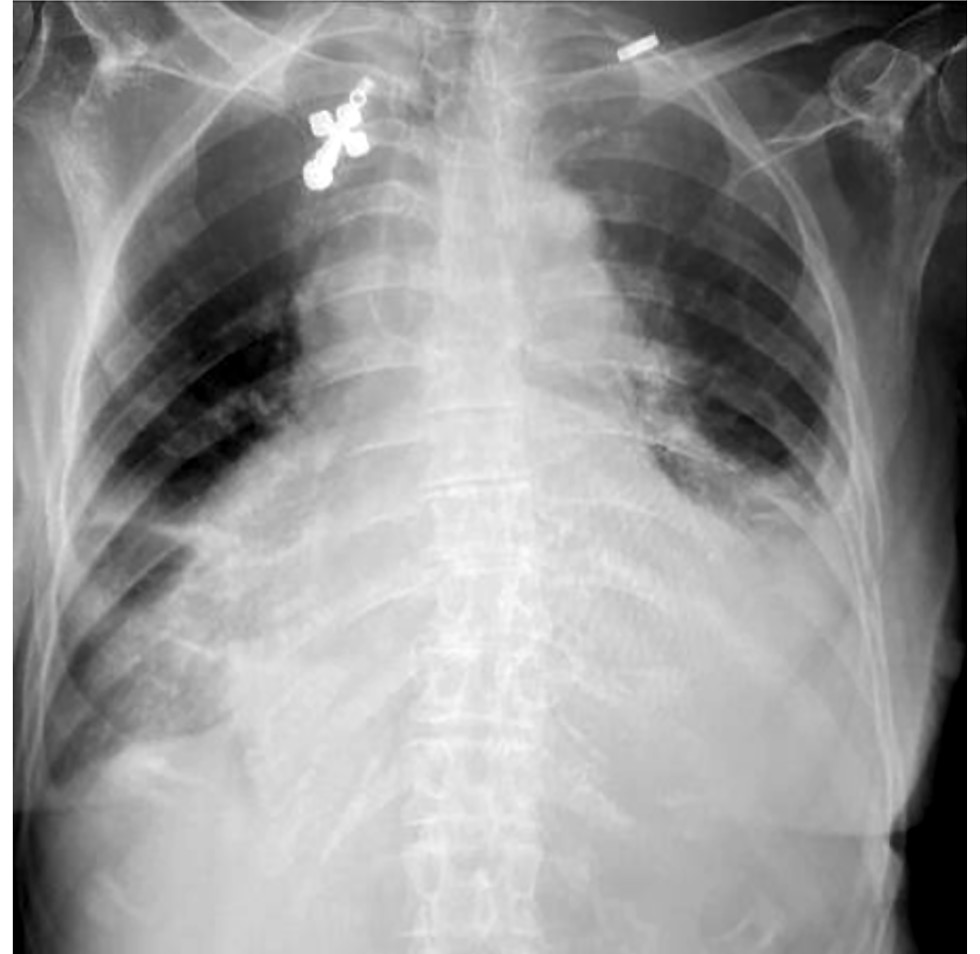

При госпитализации в отделение анестезиологии и реанимации ОККД общее состояние оценено как среднетяжёлое. По данным медицинской документации при осмотре пациентка астенического телосложения, кожные покровы и слизистые бледные, кожа влажная, периферические лимфатические узлы не увеличены, симметричные отёки стоп и голеней, частота дыхательных движений 26 в минуту, дыхание везикулярное, ослаблено, сухие единичные хрипы, перкуторный звук лёгочный, насыщение крови кислородом 93%, ритм сердца правильный с ЧСС 40 уд./мин, артериальное давление 105/70 мм рт. ст. На ЭКГ регистрировалась АВ-блокада III степени с замещающим ритмом на фоне синусовой тахикардии (118 уд./мин). Диагноз ИБС предположен в качестве наиболее вероятной причины АВ-блокады с учётом возраста и анамнеза болей в грудной клетке. Диагноз двусторонней пневмонии не снят с учётом сохраняющихся очагово-инфильтративных изменений в лёгочной ткани (рис. 4, 5). Установлен временный кардиостимулятор в режиме VVI с частотой стимуляции желудочков 60 в минуту. Продолжена терапия цефтриаксоном 1 г 2 р/сут внутривенно, назначен эноксапарин натрия 0,4 мл 2 р/сут подкожно.

Рис. 4. Рентгенограмма органов грудной клетки пациентки Б. от 31.01.2023.

Fig. 4. Chest X-ray of patient B. dated January 31, 2023.

Рис. 5. Рентгенограмма органов грудной клетки пациентки Б. от 01.02.23.

Fig. 5. Chest X-ray of patient B. dated February 1, 2023.

С учётом имеющихся клинико-анамнестических данных и результатов рентгенограммы органов грудной клетки (ОГК) от 14.01.23 (табл. 1) врачами ЦРБ установлен предварительный диагноз:

Таблица 1. Результаты рентгенологических исследований пациентки Б. Table 1. The results of X-ray examinations of patient B. | |||||

Описание | Справа в нижней доле снижение прозрачности лёгочной ткани в связи с инфильтрацией. Уровень жидкости до 4-го ребра по переднему краю в плевральной полости. Диафрагма и синусы не прослеживаются. Границы сердца значительно расширены в обе стороны | На месте сидя: с обеих сторон в нижних долях инфильтрация, корни за срединной тенью. Диафрагма и синусы не прослеживаются. Границы сердца значительно расширены в обе стороны | На месте сидя: с обеих сторон в нижних долях остаётся инфильтрация лёгочной ткани. Корни малоструктурны. Диафрагма и синусы не прослеживаются. Границы сердца значительно расширены в обе стороны | Лёгочный рисунок обогащён. Междолевая борозда справа подчёркнута. Корни малоструктурны, полнокровны, расширены. Синусы с двух сторон не просматриваются из-за жидкости. Сердце увеличено за счёт левого желудочка | Лёгочный рисунок обогащён. Междолевая борозда справа подчёркнута. Корни малоструктурны, полнокровны, расширены. Справа синус нечёткий из-за жидкости (в сравнении с 31.01.2023 положительная динамика), слева синус не просматривается (наличие жидкости). Сердце увеличено за счёт левого желудочка |

Заключение | Правосторонняя нижнедолевая пневмония, плевральный выпот | Двусторонняя нижнедолевая пневмония | Двусторонняя нижнедолевая пневмония в фазе разрешения | Двусторонний гидроторакс | Двусторонний гидроторакс |